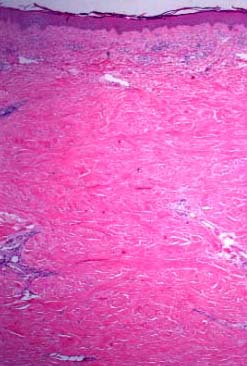

The dermis in scleredema is about three times thicker than normal . The collagen bundles are thickened and separated by clear spaces, causing "fenestration" of the collagen. The secretory coils of the sweat glands, surrounded by fat tissue, are located in the upper dermis or mid dermis rather than, as normally, in the lower dermis or at the junction of the dermis and the subcutaneous fat. Because the distance between the epidermis and the sweat glands is unchanged, it can be concluded that much of the subcutaneous fat in scleredema has been replaced by dense collagenous bundles . No increase in the number of fibroblasts is noted in association with the hyperplasia of the collagen; in fact, their number may be strikingly decreased .

Differential Diagnosis. It can be difficult to differentiate between end-stage scleroderma in which inflammation is no

|

longer present and scleredema. As a rule, however, in scleroderma, the collagen in the reticular dermis and subcutaneous tissue appears homogenized and hyalinized and stains only lightly with eosin and with the Masson trichrome stain, but in scleredema, the collagen bundles are thickened without being hyalinized and stain normally with eosin and the trichrome stain . A marked increase in type 1 collagen gene expression occurs in scleroderma, leading to increased collagen synthesis